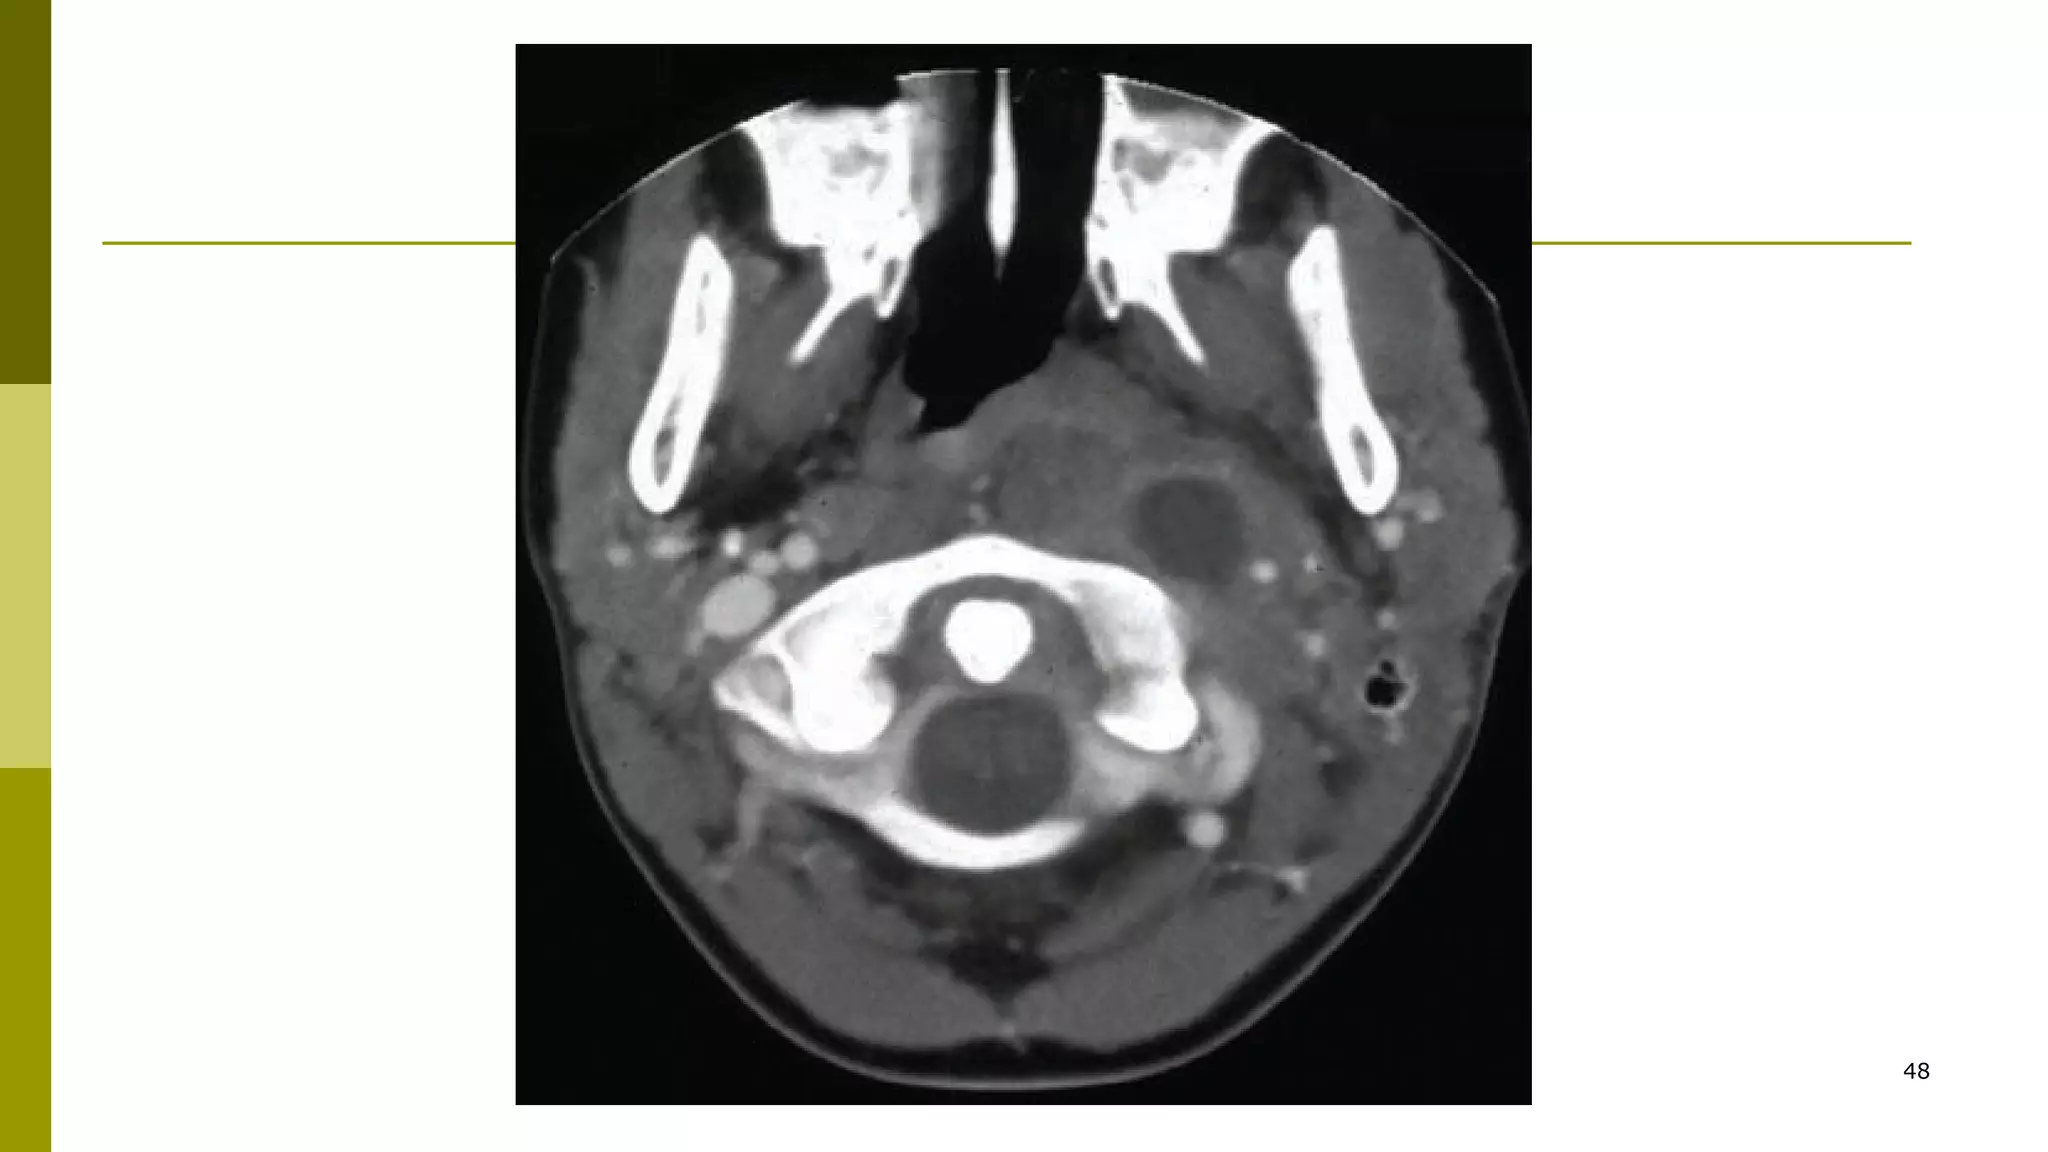

Peritonsilar abscess CT scan with contrastPeritonsilar abscess CT scan with contrast

is indicated in general for unusualis indicated in general for unusual

presentation(e.g. inferior pole abscess)presentation(e.g. inferior pole abscess)

and for pts at high risk of drainageand for pts at high risk of drainage

procedures.procedures.

CTscan may be used to guide needleCTscan may be used to guide needle

aspiration for draining PTA.aspiration for draining PTA.

48